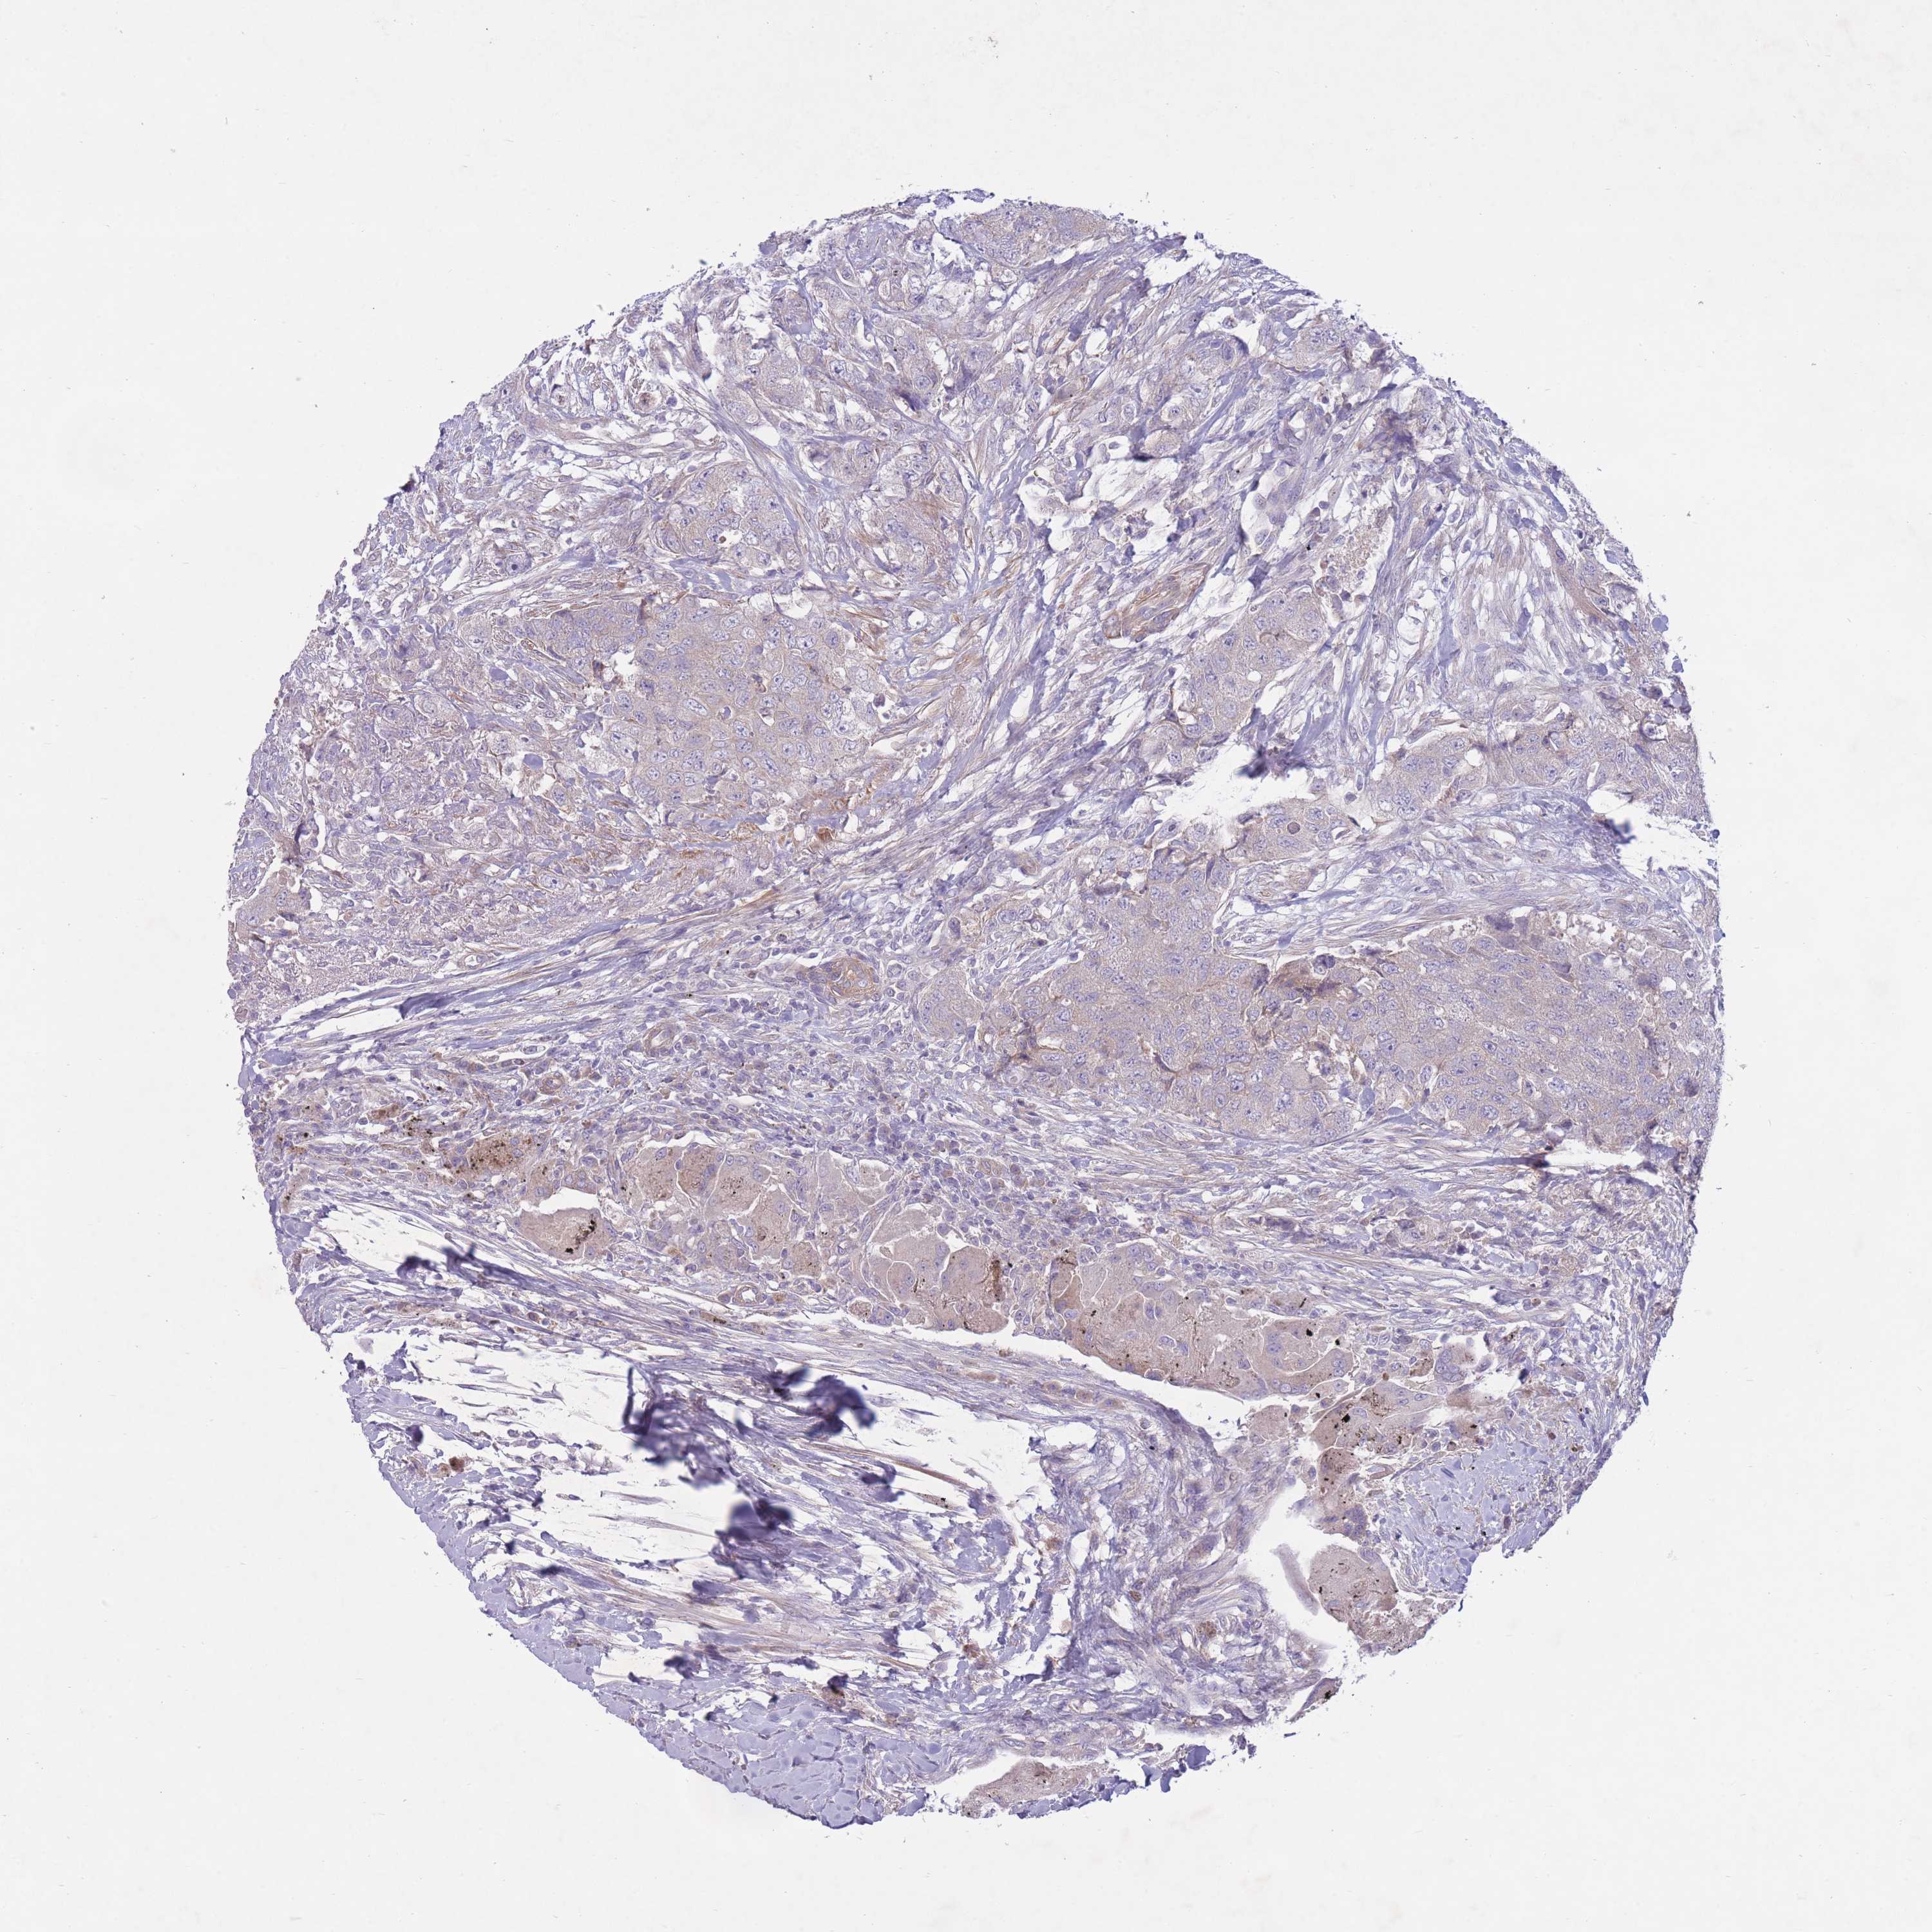

UROTHELIAL CANCER - Protein expressioni

A mouse-over function shows sample information and annotation data. Click on an image to view it in a full screen mode. Samples can be filtered based on level of antibody staining by selecting one or several of the following categories: high, medium, low and not detected. The assay and annotation is described here.

Note that samples used for immunohistochemistry by the Human Protein Atlas do not correspond to samples in the TCGA dataset.

Antibody stainingi

Antibody staining in the annotated cell types in the current human tissue is reported as not detected, low, medium, or high, based on conventional immunohistochemistry profiling in selected tissues. This score is based on the combination of the staining intensity and fraction of stained cells.

Each image is clickable and will lead to virtual microscopy that enables deeper exploration of all samples and also displays staining intensity scores, fraction scores and subcellular localization as well as patient and tissue information for each sample.

Antibody HPA050409

Antibody HPA054211

Urothelial carcinoma, Low grade

Urothelial carcinoma, High grade

Urothelial carcinoma, NOS